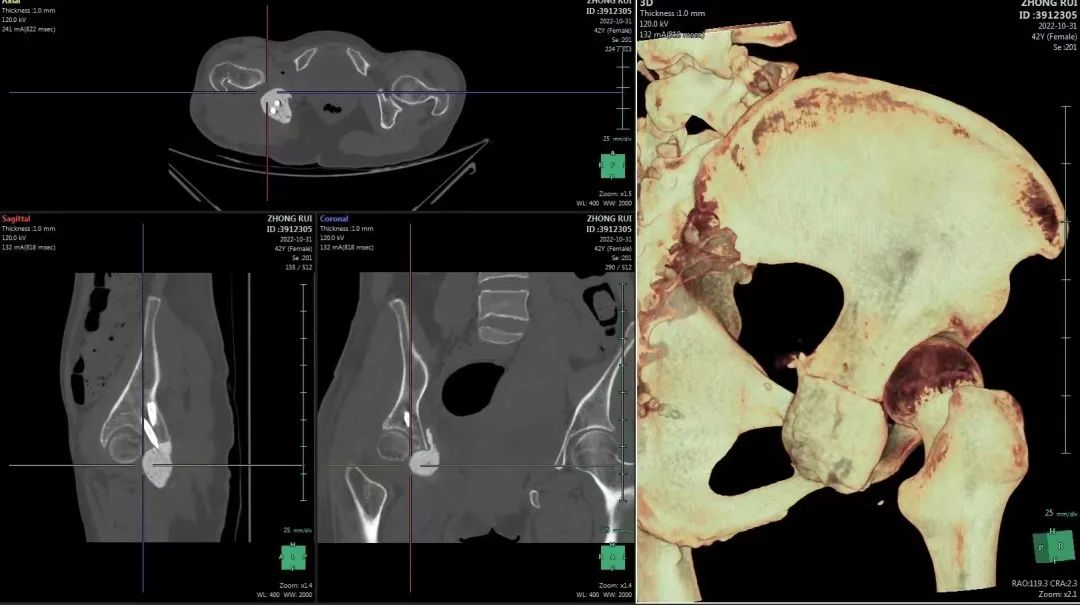

3D打印+数字化模拟 助力肿瘤精准切除

杨团民主任医师带领团队反复讨论,结合患者的病理结果,通过术前数字化模拟,决定在肿瘤与髋臼侧,距离肿瘤上缘约1cm处截骨,切除约1/4髋臼,即右侧骨盆部分II区+III区切除,在肿瘤完整切除的情况下,尽可能多的保留患者髋臼部位,提高了疗效也改善预后。

(术前数字化模拟肿瘤大小及部位、3D打印设计导板辅助术中截骨,手术效果更精确)

通过术前规划手术路径及肿瘤切除范围,以及重要部位的精准参数,西安市红会医院骨病肿瘤科为患者制定了个体化治疗方案,杨团民主任医师主刀顺利实施了“右侧坐骨软骨肉瘤瘤体切除、血管、神经探查、髋臼周围重建术”,肿瘤完整切除,体积约9cmx8cmx6cm。剖开标本显示肿瘤浸润边界距离正常髋臼侧骨组织1cm,肿瘤边界切除精准。